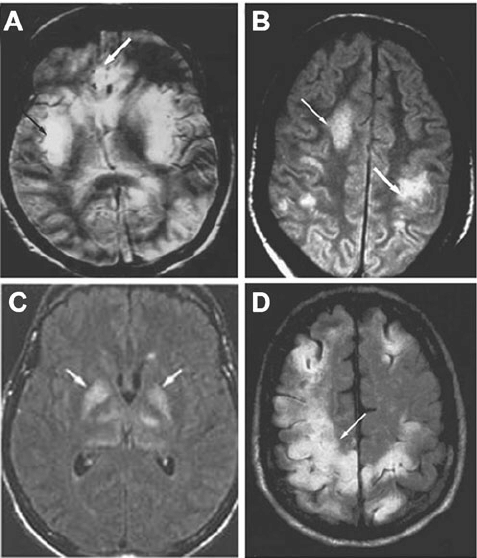

Encephalitis refers to inflammation of the brain parenchyma secondary to infectious or autoimmune causes. The patient can present with both physical and cognitive signs and symptoms. The physical characteristics of encephalitis are: - Fever - Neck stiffness - Photophobia - Headache - Seizures - Sound sensitivity - Altered consciousness - Movement disorders - Partial paralysis of limbs - Diplopia - Impaired speech - Impaired hearing - Coma The major cognitive features are: - Drowsiness - Disorientation - Confusion - Anxiety - Loss of memory behavioral changes - Impaired cognition - Hallucination Reference: https://www.hopkinsmedicine.org/health/conditions-and-diseases/encephalitis Image via: https://www.researchgate.net/publication/51816352_Neuro-Intensive_Care_of_Patients_with_Acute_CNS_Infections/figures?lo=1&utm_source=google&utm_medium=organic